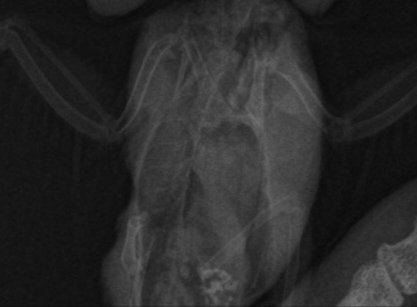

Вывих крыла и неоплазия

Помогите пожалуйста разобраться, птицу купили 2 недели назад, писала тут, что он не может летать, поняли это когда впервые попробовали выпустить. Сегодня дождались записи ветеринара, он посмотрел птицу, сделал снимок, сказал, что это вывих. Описание снимка сказали подождать, будет после того, как специалист из другого города опишет. В итоге вечером мне прислали описание снимка, прилагаю текст и теперь я совсем не понимаю. Там и травма и но образование. В ветеринарной клинике, где мы были молчат, больше никаких консультаций не дали мне. Можно ли что-то понять по приложенному сниму и описанию? Я верно понимаю, что дело не только в вывихе, а по снимку обнаружена какая-то опухоль?